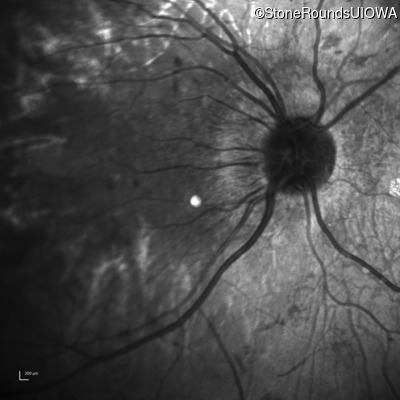

Infrared Fundus Photograph - Right - 20/200 +1

Exemplar